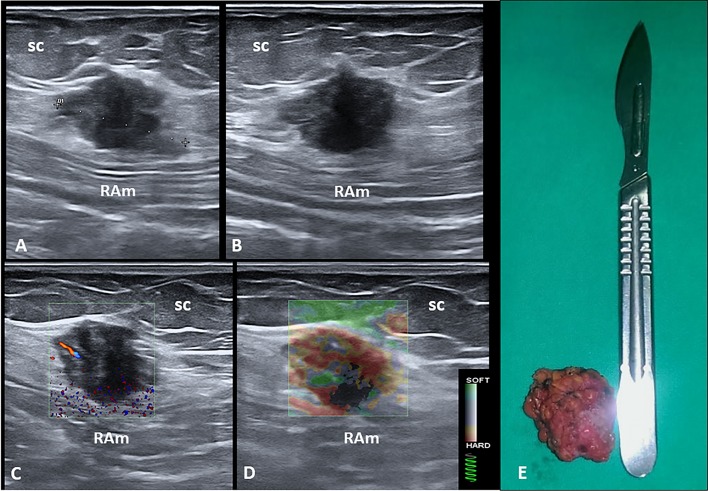

Sonographic examination of the abdominal wall revealed, in the right inguinal region and at the level of the subcutaneous tissue, a heterogeneous hypoechoic mass with echogenic intralesional spots (Fig. 1). The nodule was precisely located beneath the cesarean surgery scar and superficial to the rectus abdominis muscle fascia. Color Doppler examination showed the presence of intralesional vascular spots, and strain elastosonography revealed a hard pattern compared to the surrounding tissues (Fig. 1).

Fig. 1.

Long (a) and short (b) axis B-mode ultrasound (US) images show the hypoechoic nodule located between the subcutaneous tissue (sc) and the muscular plane of the abdominal wall. Fine intralesional vascular spots are depicted using the color-power Doppler mode (c), and a hard pattern of the mass is clearly identified with the strain elastosonography modality (d). The macroscopic appearance of the corresponding surgical specimen after complete excision (e). RAm rectus abdominis muscle

Patients were referred for surgical treatment with complete excision of the masses (Figs. 1 and 2). The histological examination of the surgical specimens revealed benign endometrial glands and stromal tissues, thus confirming the diagnosis of endometriosis. Free surgical margins of 1 cm were histologically demonstrated in order to prevent local recurrence of the pathology. Note that the histopathological pattern also showed multiple widespread hemorrhagic foci inside the mass. The patients were discharged after uneventful hospital courses.

In our patients, transabdominal US allowed the identification of pathological masses not otherwise detectable with a normal physical examination. Also, tenderness in the site of the probe’s pressure and the location of the masses in relation to the surgical scar directed the diagnostic suspicion toward extrauterine endometriosis. Specifically, US examination showed hypoechoic masses with well-defined boundaries (benignity criterion), but with intralesional vascularization (malignancy criterion). Moreover, strain elastography produced a different echostructural pattern with respect to the surrounding tissue, thus confirming the ectopic nature of the masses.

Few previous works have investigated the role of elastography in endometriosis, and some authors have demonstrated that sonoelastography has high sensitivity and specificity for distinguishing endometrioma from hemorrhagic ovarian cysts [20]. Previously published papers have also evaluated elastography in diagnosing cesarean section scar endometrioma and have shown that the endometrioma presents a typical blue–green–red appearance with clearly defined outer borders (i.e., red and green areas correspond to the central hypoechoic soft areas) [21].

In our opinion, the two clinical cases demonstrate how a simple and repeatable method such as US allowed us to diagnose the abdominal wall masses that would not have been detected with a simple physical examination. Furthermore, the US study performed with a high-resolution linear probe allowed us to examine all the characteristics of the masses (structure, margins, ratios, and vascularization), avoiding the use of advanced imaging methods such as CT and magnetic resonance, which have known side effects [22]. The use of strain elastosonography allowed a qualitative estimate of the stiffness of the ectopic tissue. The main limitation of US, and of all imaging methods, is that the examination is not conclusive enough for a specific histopathological diagnosis. Therefore, since these US methods have the same diagnostic accuracy with lower cost and time requirements and fewer side effects, they seem to be the method of choice for the diagnosis of endometriotic pathology in the abdominal wall, in combination with an accurate past medical history (cyclic abdominal pain and specific pain localization next to the CS scar).